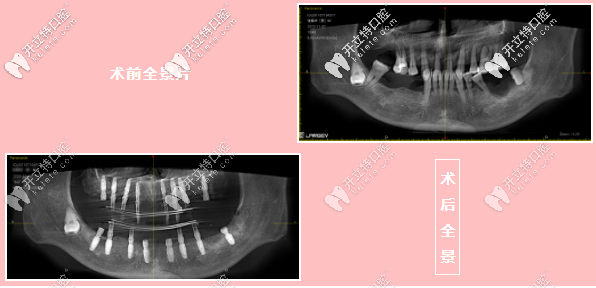

陳先生術(shù)前術(shù)后全景對(duì)比圖

【術(shù)前術(shù)后對(duì)比圖】

據(jù)維樂(lè)曾志威院長(zhǎng)描述,陳先生的口腔情況不容樂(lè)觀:由于陳先生牙齒陸續(xù)脫落,牙槽骨吸收情況不一樣,導(dǎo)致骨面凹凸不平,有的位置缺骨較多。

像這樣骨質(zhì)情況的種植手術(shù)受到極大的限制,一方面要大量植骨,增加了種植失敗的風(fēng)險(xiǎn),另一方面加倍延長(zhǎng)了種植戴牙時(shí)間。

但憑借曾院長(zhǎng)豐富的經(jīng)驗(yàn)以及對(duì)手術(shù)的把控,整個(gè)手術(shù)歷時(shí)3個(gè)多小時(shí),成功完成本次集高難度、高精度于一體的綜合性種植牙手術(shù),并且制作臨時(shí)過(guò)渡義齒。